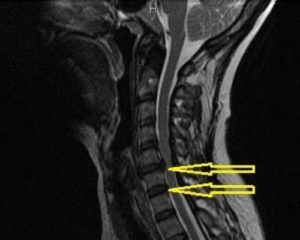

Запущенная стадия остеохондроза, перенесенные травмы, специфические условия труда, возрастные изменения, нарушение осанки и гиподинамия – это причины провоцирующие возникновение грыжи шейного отдела позвоночного ствола.

Шейный отдел состоит из 7 позвонков, которые обозначают буквой C и порядковым номером (с1-с7), между ними расположены диски, они осуществляют амортизационную функцию.

В результате разрыва фиброзного кольца диска, которому предшествует протрузия, наружу выходит его сердцевина (пульпозное студенистое ядро) – образуется грыжа.

Грыжа, возникшая в области диска с4-с5, приводит к ущемлению нервного корешка (пятого с левой, правой стороны), это происходит вследствие сужения отверстий спинномозгового канала, из которых выходят нервные окончания.

Симптомы, возникающие при грыже диска с4-с5 – это ощущение слабости в предплечье, руках. Болевой синдром в дельтовидной мышце плеча, онемение, снижаются мышечные рефлексы. Болевые симптомы возникают при сгибании рук в локтевом суставе, отведении их назад. Ухудшается подвижность шеи в области пораженного диска.

Межпозвонковая грыжа шейного отдела позвоночника сдавливает кровеносные сосуды, чем ухудшает кровоснабжение, насыщение кислородом и питание головного мозга.

Симптомы этого – головные боли, головокружение, ухудшение координации, памяти.